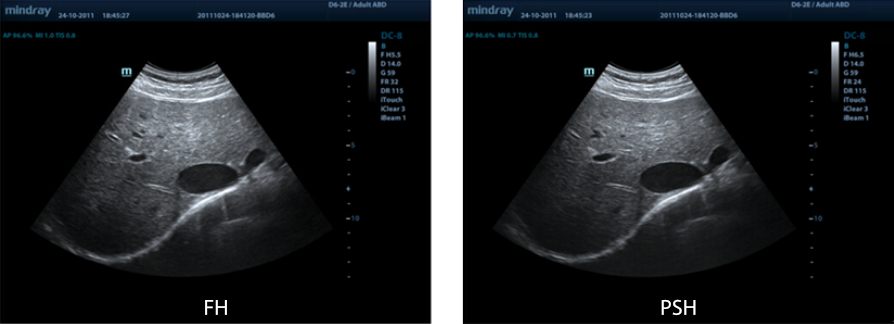

PSHI? (Phase Shift Harmonic Imaging- Faz Kaymal? Harmonik G?rĂŒntĂŒleme)

MĂŒkemmel ??zĂŒnĂŒrlĂŒk ve daha az gĂŒrĂŒltĂŒ ile daha temiz g?rĂŒntĂŒleri sa?layan daha iyi kontrast ??zĂŒnĂŒrlĂŒ?ĂŒ i?in PĂŒrifiye Harmonik G?rĂŒntĂŒleme.